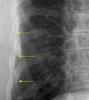

사진은 AP, both oblique 총 3장을 찍습니다. 공기 영상에서는 뼈가 잘 보이지 않는 경우도 많기 때문에 이전처럼 인화지인 경우에는 뒤쪽에 추가로 전등을 켜고 보기도 합니다. 최근의 PACS에서는 정확한 관찰을 위해 음영을 조절하거나 filter를 넣기도 하며 marginal enhancement 기능을 활용하기도 합니다. 이런 방법은 늑골뿐 아니라 다른 부위의 희미한 영상을 볼 때도 도움이 됩니다.

X-ray : 갈비뼈 골절(Rib fracture)